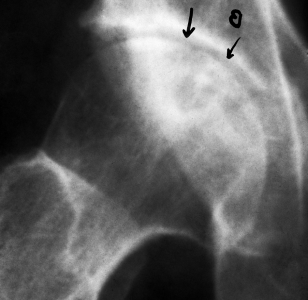

病例1男,29岁,患病2年,治疗15个月痊愈。治疗前,股骨头顶部塌陷、变平,顶部可见大块坏死骨,密度增高(a)。经过9个月的治疗,死骨与正常骨融合,密度减低,表面不清楚(b)。治疗后,股骨头略平,骨密度均匀,骨小梁清晰(c)

Case 1 male, 29 years old, 2 years sick, 15 months after eating. Before eating, the top of the femoral head collapsed, flattened, the top of the large dead bone, increased density, uneven thickness (a). After 9 months of treatment, the dead bone fused with the normal bone, the density decreased and the surface was unclear (b). After eating, the femoral head is slightly flat, the bone density is even, and the bone trabecula is clear (c).

病例2,66岁,患病8年,治愈16个月修复。治疗前股骨头平坦,关节面粗糙,间隙消失,密度不均,有椭圆形死骨量(a)。进食后,关节间隙出现,关节表面光滑,骨密度恢复(b)

Case 2, 66 years old, 8 years sick, 16 months cured. Before eating, the femoral head was flat, the articular surface was rough, the space disappeared, the density was uneven, there were oval dead bone mass (a). After eating, the joint space appeared, the joint surface was smooth, and the bone density recovered (b)